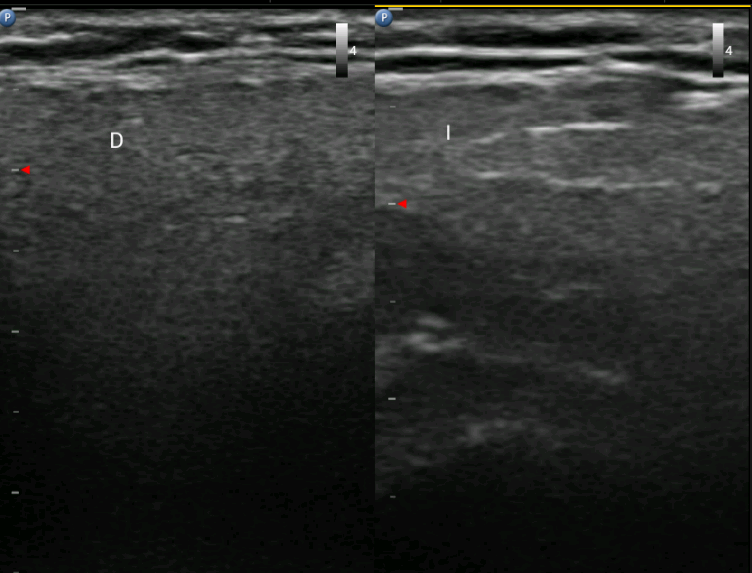

Hallazgos ecográficos

En la ecografía clínica se objetiva morfología del parénquima parotídeo y submandibular engrosado, con ecogenicidad aumentada y pérdida de atenuación posterior en lado derecho respecto a contralateral. No se objetiva captación de Doppler ni adenopatías de significado patológico.